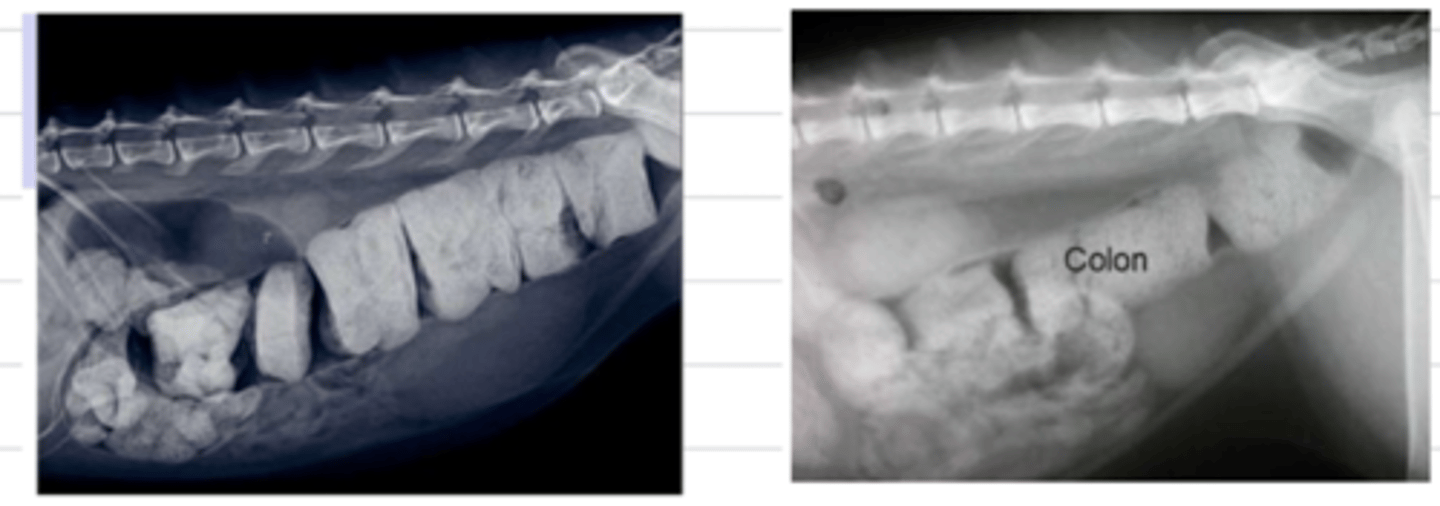

constipation

hard, dry stools accumulated in the colon/rectum

what do we see here?

a dilated colon, common in cats and due to constipation. it causes smooth muscle contraction disorders, leading to hypomotility. it is irreversible if it is chronic.

what is megacolon?